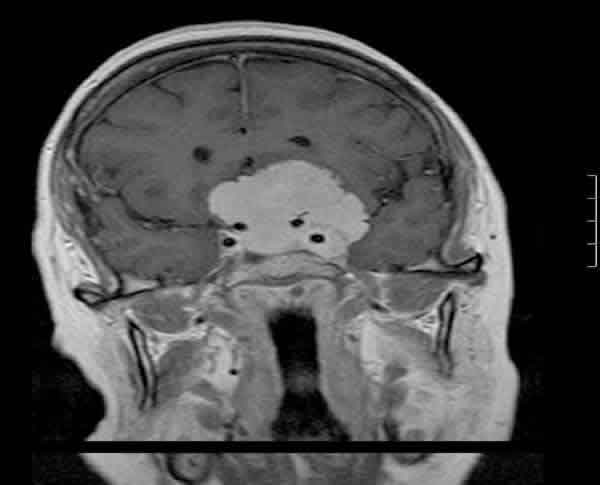

Se solicitó una resonancia nuclear magnética (RNM) con gadolinio urgente que mostró la presencia de un meningioma supra e infraselar de 5x4,3x4,8 cm sobre la silla turca, línea media cerebral anterior, alas menores del esfenoides y apófisis clinoides, con extensión hacia el seno cavernoso izquierdo y englobando la arteria carótida interna izquierda sin llegar a estenosarla, desplazamiento de la hipófisis y el hipotálamo, con un leve edema del lóbulo frontal (fig. 4). También presentó extensión hacia el ápex orbitario izquierdo a través de la fisura orbitaria, encontrándose el nervio óptico y su vaina engrosados y con signos de congestión venosa (fig. 5).

Fig. 5. Extensión hacia el ápex orbitario izquierdo a través de la fisura orbitaria, encontrándose el nervio óptico y su vaina engrosados y con signos de congestión venosa (imagen potenciada en T2).